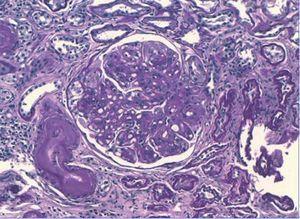

Se inició tratamiento depletivo con diuréticos, inhibidores de la enzima de conversión de la angiotensina (IECA) y antagonistas de los receptores de angiotensina II (ARAII), estatinas, heparina de bajo peso molecular, y se recomendó mejorar el control glucémico. Debido a la hidronefrosis del riñón izquierdo provocada por un síndrome de la unión pieloureteral se realizó pieloplastia y se colocó una nefrostomía percutánea en el riñón izquierdo. A pesar de estas medidas el paciente requirió nuevos ingresos hospitalarios por descompensación del síndrome nefrótico, con incremento de la creatinina plasmática a 2,5-3 mg/dl y persistencia de la proteinuria nefrótica, motivo por el que se decide iniciar programa de hemodiálisis. Aunque la sospecha inicial fue de ND, estando el paciente en hemodiálisis persistió el mal control volumétrico y con parámetros bioquímicos de actividad del síndrome nefrótico decidimos realizar una biopsia renal para descartar una glomerulopatía asociada. Los hallazgos de biopsia fueron: 12 glomérulos por plano de corte, cinco de ellos completamente esclerosados. Todos los glomérulos estudiados mostraban una expansión mesangial con formación de nódulos acelulares (Kinmelstein-Wilson). La inmunofluorescencia fue negativa. En el intersticio se observó una fibrosis moderada con focos de atrofia tubular asociada. El componente vascular mostró una llamativa hialinosis de su pared, siendo el diagnostico anatomopatológico final compatible con una glomeruloesclerosis difusa (figura 1) y nodular (figura 2), con sustrato morfológico de enfermedad diabética.

Figura 2. Técnica de hematoxilina-eosina (x40 aumentos): glomeruloesclerosis nodular típica.